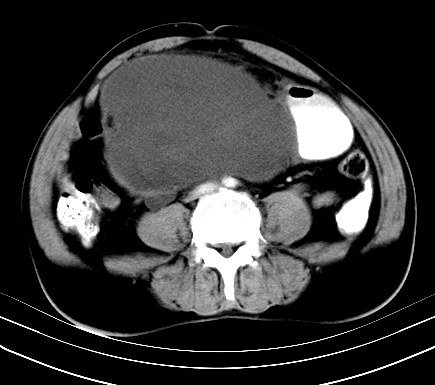

标题: CT19729B:男,74岁,因腿疼就诊,查体触腹部肿物,

增强扫描

动脉期

【ct表现】

1、肿块巨大,往往位于腹膜后,长大后才引起症状而就诊;那么位于腹膜后的肿瘤80%为恶性肿瘤。

2、实性肿瘤,增强扫描轻度不均强化,实性肿瘤一般不是好东西。

3、肿瘤边缘似见少许脂肪样密度。

4、腹膜后未见肿大淋巴结,但肿瘤于临近的肠管及组织接触紧密。

【诊断】

腹部占位,考虑位于腹膜后的恶性肿瘤,脂肪肉瘤(实体型)可能性大。

【分析】

1、腹膜后的肿瘤少见,但种类繁多,包括脂肪肉瘤、纤维组织细胞肉瘤、纤维肉瘤、平滑肌肉瘤、恶性畸胎瘤、神经肉瘤、神经母细胞瘤、血管肉瘤及横纹肌肉瘤等,其中脂肪肉瘤为较常见的一种肿瘤。

2、增强扫描强化不明显,除脂肪肉瘤以外,一般肿瘤强化中度以上。脂肪肉瘤可不强化或轻度强化。

术后病理结果:腹膜后脂肪肉瘤。